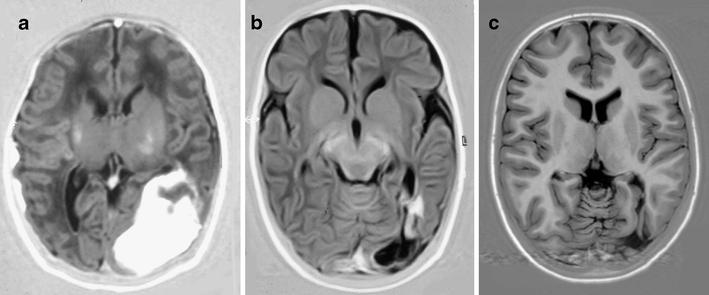

Seventeen of the 53 term infants had infratentorial ICH, 20 had supratentorial ICH, and 16 had a combination of the two. Seizures were the most common presenting symptom (71.7%), another ten infants (18.9%) presented with apneic seizures, and five infants had no clinical signs but were admitted to our NICU because of perinatal asphyxia (n=2), respiratory distress (n=2), and development of posthemorrhagic ventricular dilatation (n=1). Continuous amplitude-integrated electroencephalography recordings were performed in all infants. Clinical or subclinical seizures were seen in 48/53 (90.6%) infants; all received anti-epileptic drugs. Thirteen of all 53 (24.5%) infants died. The lowest mortality rate was seen in infants with supratentorial ICH (10%). Three infants with a midline shift required craniotomy, six infants needed a subcutaneous reservoir due to outflow obstruction, and three subsequently required a ventriculoperitoneal shunt. The group with poor outcome (death or developmental quotient (DQ) <85) had a significantly lower 5-min Apgar score (p=.006). Follow-up data were available for 37/40 survivors aged at least 15 months. Patients were assessed with the Griffiths Mental Developmental Scales, and the mean DQ of all survivors was 97 (SD=12). Six infants (17%) had a DQ below 85 [two of them had cerebral palsy (CP)]. Three infants developed CP (8.6%); one had cerebellar ataxia, and two had hemiplegia.

ICH with parenchymal involvement carries a risk of adverse neurological sequelae with a mortality of 24.5% and development of CP in 8.6%. The high mortality rate could partly be explained by associated perinatal asphyxia. Infants with supratentorial ICH had a lower, although not significant, mortality rate compared with infants with infratentorial ICH and infants with a combination of supratentorial ICH and infratentorial ICH. In spite of often large intraparenchymal lesions, 30 of the 34 survivors without CP (88.2%) had normal neurodevelopmental outcome at 15 months.